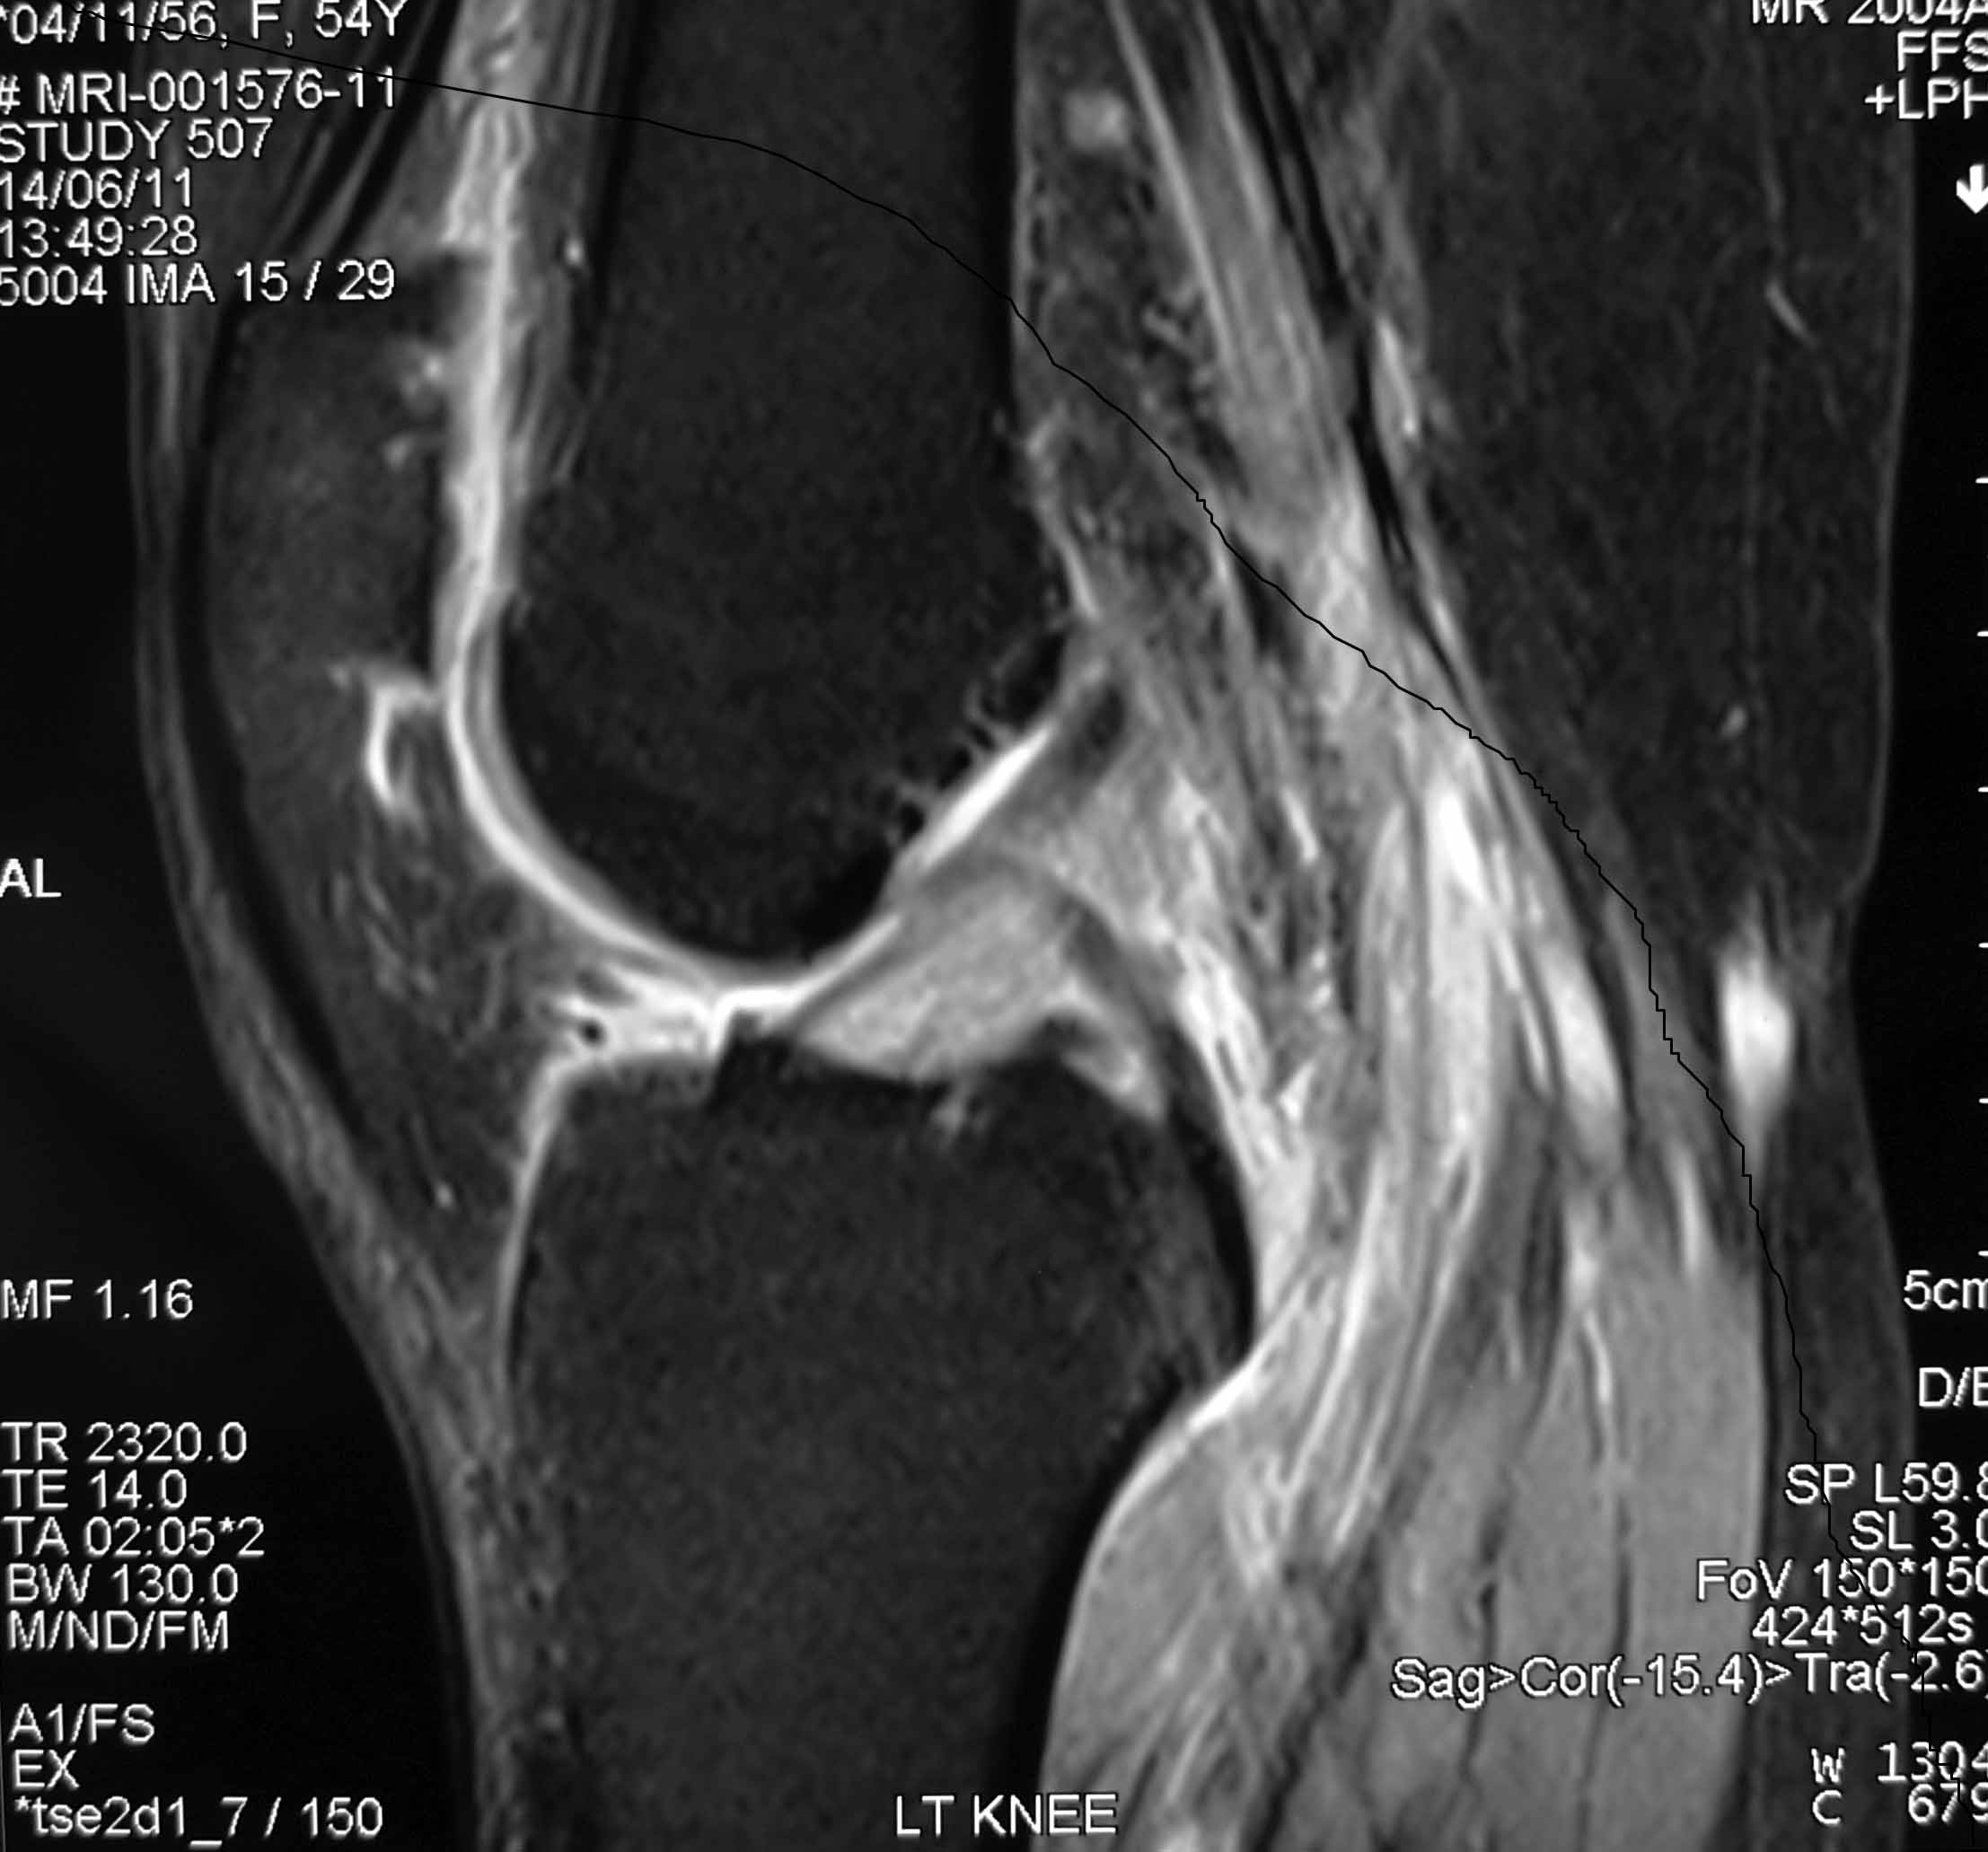

This is basically an MRI diagnosis of expansion and increased signal of an intact ACL in a person with knee pain which is worse on knee flexion/bending.

The MR-findings of mucoid degeneration of the ACL include:

- an ill-defined ACL

- an increased ligamentous girth

- a normal orientation of the ligament and an increased signal intensity on all sequences interspersed among visible intact ACL fibers (“celery stalk” appearance).

Mucoid degeneration of the ACL should be considered when an apparently thickened and ill-defined ACL with increased signal intensity on all sequences is identified in a patient with a clinically intact ACL.